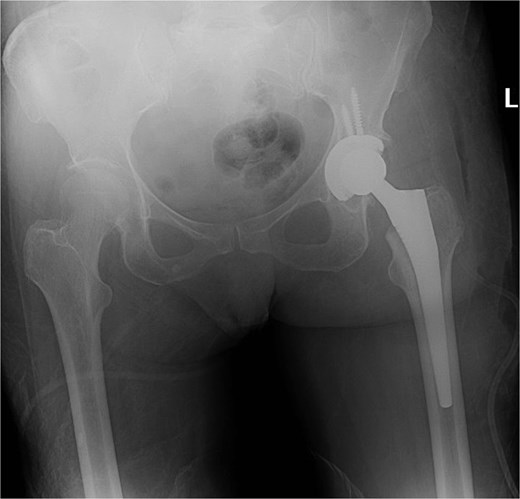

Five days after the first DAIR procedure, the patient was taken to the operating room for the second DAIR and removal of previously applied antibiotic beads. No purulence was encountered and all tissues were healthy. The femoral head and acetabular liner were removed and discarded. Multiple tissue and fluid culture were again taken. Thorough brushing was done at the modular interfaces. The wound was soaked with betadine solution and again irrigated with pulse lavage using 9 l of normal saline. Gowns and gloves were changed by all surgical staff. Draping was done using sterile drapes over the previous drapes and a new set of surgical instruments was utilized for the remainder of the procedure. A new femoral head and acetabular liner were applied. Post-op imaging showed the hip prosthesis in adequate alignment (Fig. 4).

X-ray of the pelvis showing metallic hardware in good position.